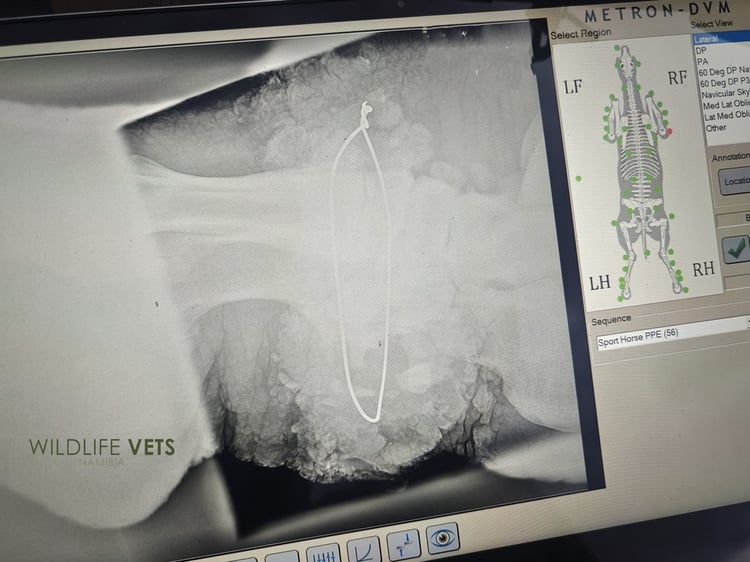

The rhino cow was sedated and while it was snoring in deep slumber, the X-rays showed that the poor animal had been carrying around a wire snare used by poachers, for years inside its leg.

“The rhino had probably escaped at that time and the wound healed as tissue formed around the wire snare. The animal has coped quite well all these years,” according to Wildlife Vets Namibia (WVN).

The wire loop had unfortunately had over the years cut through the tissue almost to the bone!

The wound was opened on the one side, and after some searching the entire wire snare was found instead of suspected bits and pieces of the wire.

The round snare was cut and and gently pulled out of the rhino's leg.